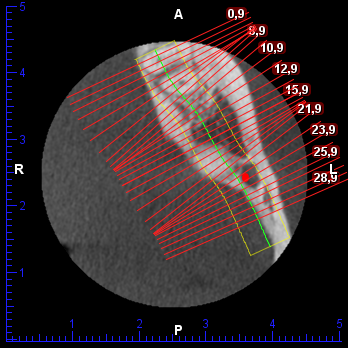

Allego il 3d del primo dente

[ 1.37 MiB | Osservato 869 volte ]

e del secondo

[ 1.24 MiB | Osservato 869 volte ]